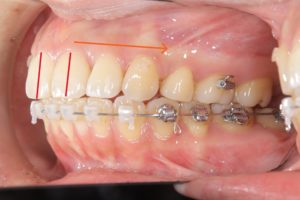

矯正治療前

赤い線が切端ライン

青い線が歯頚部ラインです。

抜歯後8カ月経過

唇側に向いていた切端ラインが

抜歯後内側(口蓋側)に向いています。

このように前歯を後退できるのは

精密検査時のCTデータで

骨の厚み、歯根の位置を立体的に把握し

前歯を下げても骨や歯肉に無理が生じないことを

事前に確認した上で治療を行うからです。